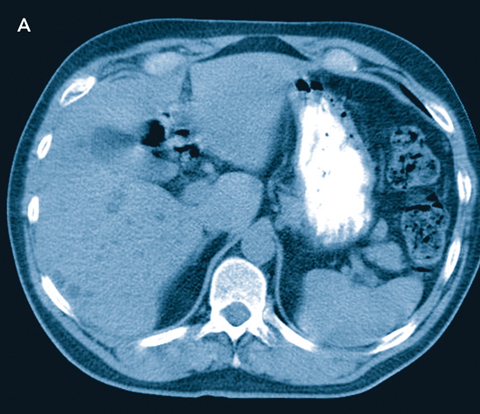

A 57-year-old man had a colonoscopy which revealed a partially obstructing polyp in the rectum. Biopsy revealed an adenocarcinoma. A computed tomography scan of the abdomen revealed multiple low-attenuation lesions diffusely throughout the liver (Box). Differential considerations included multiple small hepatic cysts, Caroli’s disease, microabscesses and metastases. The patient had a low anterior resection for his rectal tumour and wedge biopsy of the liver. Macroscopically, there were multiple 2–3 mm white nodular lesions throughout the liver, with the macroscopic appearance of diffuse liver metastases. Pathology of the liver biopsy revealed von Meyenberg complexes.